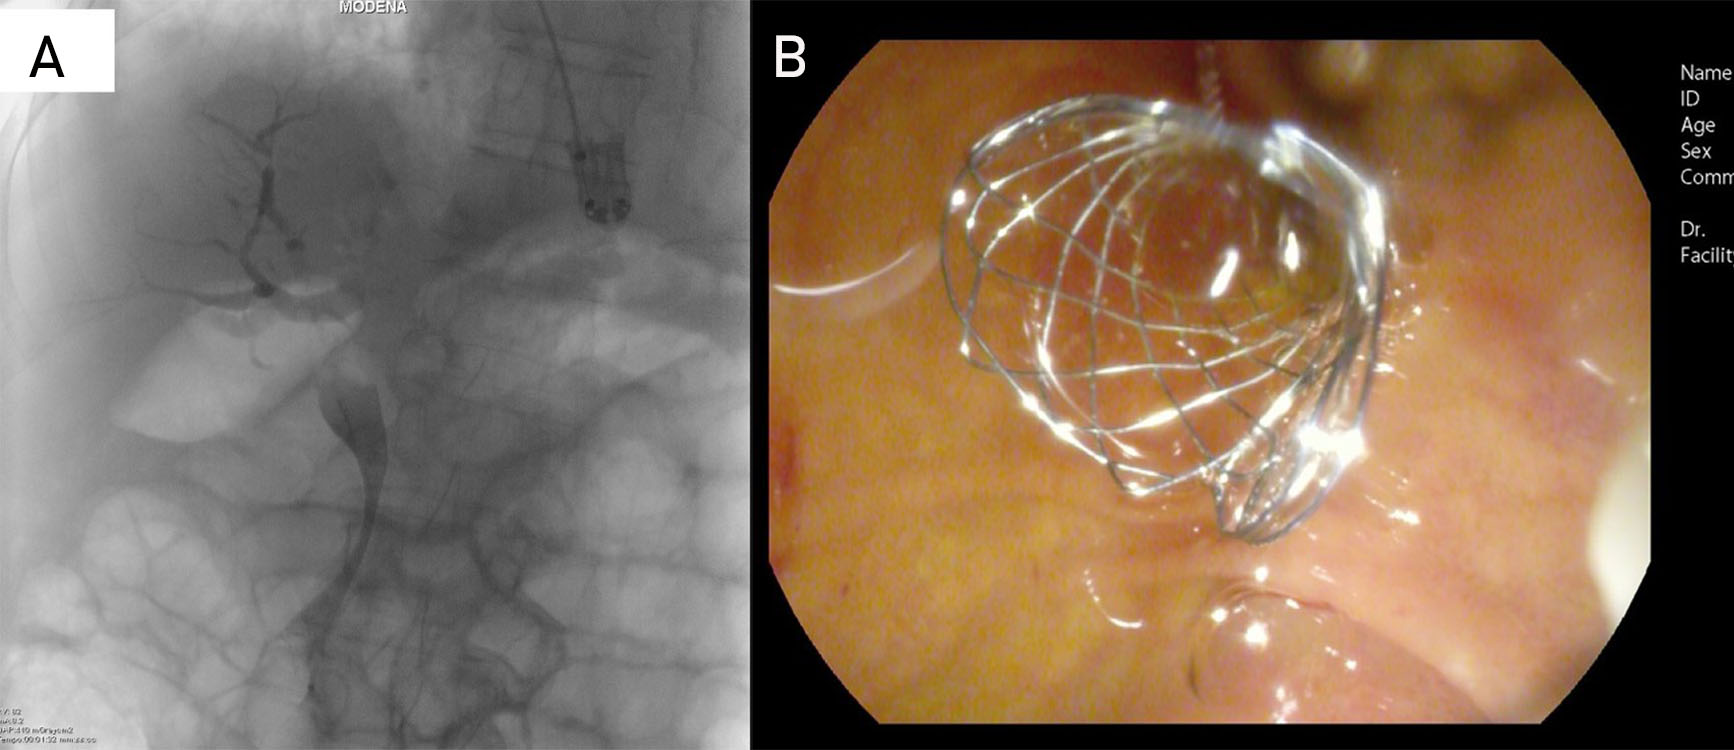

All patients underwent ERCP in the supine or lateral position using a standard duodenoscope. After successful biliary access, minimal biliary sphincterotomy was performed in all patients prior to metal stent insertion. The length of the stent was chosen according to the extension of the stricture in order to release the proximal end 1–2 cm beyond the stricture, and always below the hilum, with the distal uncovered portion outside the papilla. After estimating the length of the stricture during cholangiography (Figure 2), the endoscopist chose between the available types of Niti-S Biliary Covered stent (Both Bare Type) (Taewoong Medical Co. Ltd., Korea) (diameter of 10 mm and length from 4 to 8 cm) (Figure 3A and 3B).

Figure 3

Figure 3. Fluoroscopic image and endoscopic image. A. Placement of a 6 cm-long Niti-S Partially covered self-expandable metal stent. B. Placement of a 6 cm-long Niti-S Partially covered self-expandable metal stent.